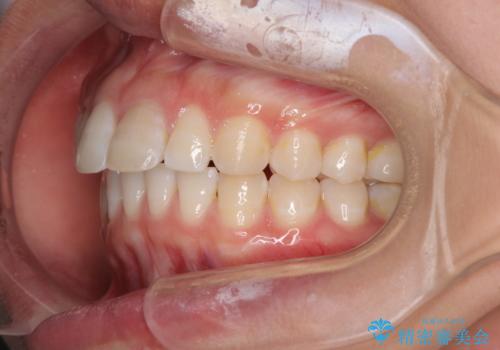

前歯を整えたい 小さい前歯がある 矯正・セラミック併用で美しく インビザラインでも抜歯矯正できます

総合歯科治療 矯正治療と失活歯のセラミック補綴治療

欠損歯と矮小歯 矯正治療と前歯のセラミック治療